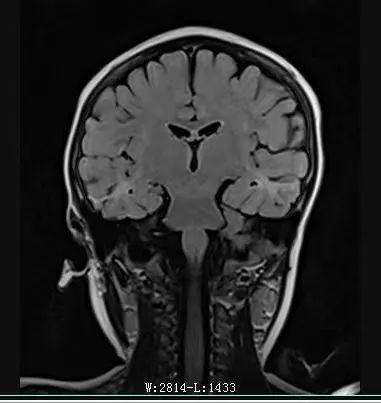

MRI:雙側(cè)額葉,雙側(cè)顳葉異常信號(hào)伴萎縮